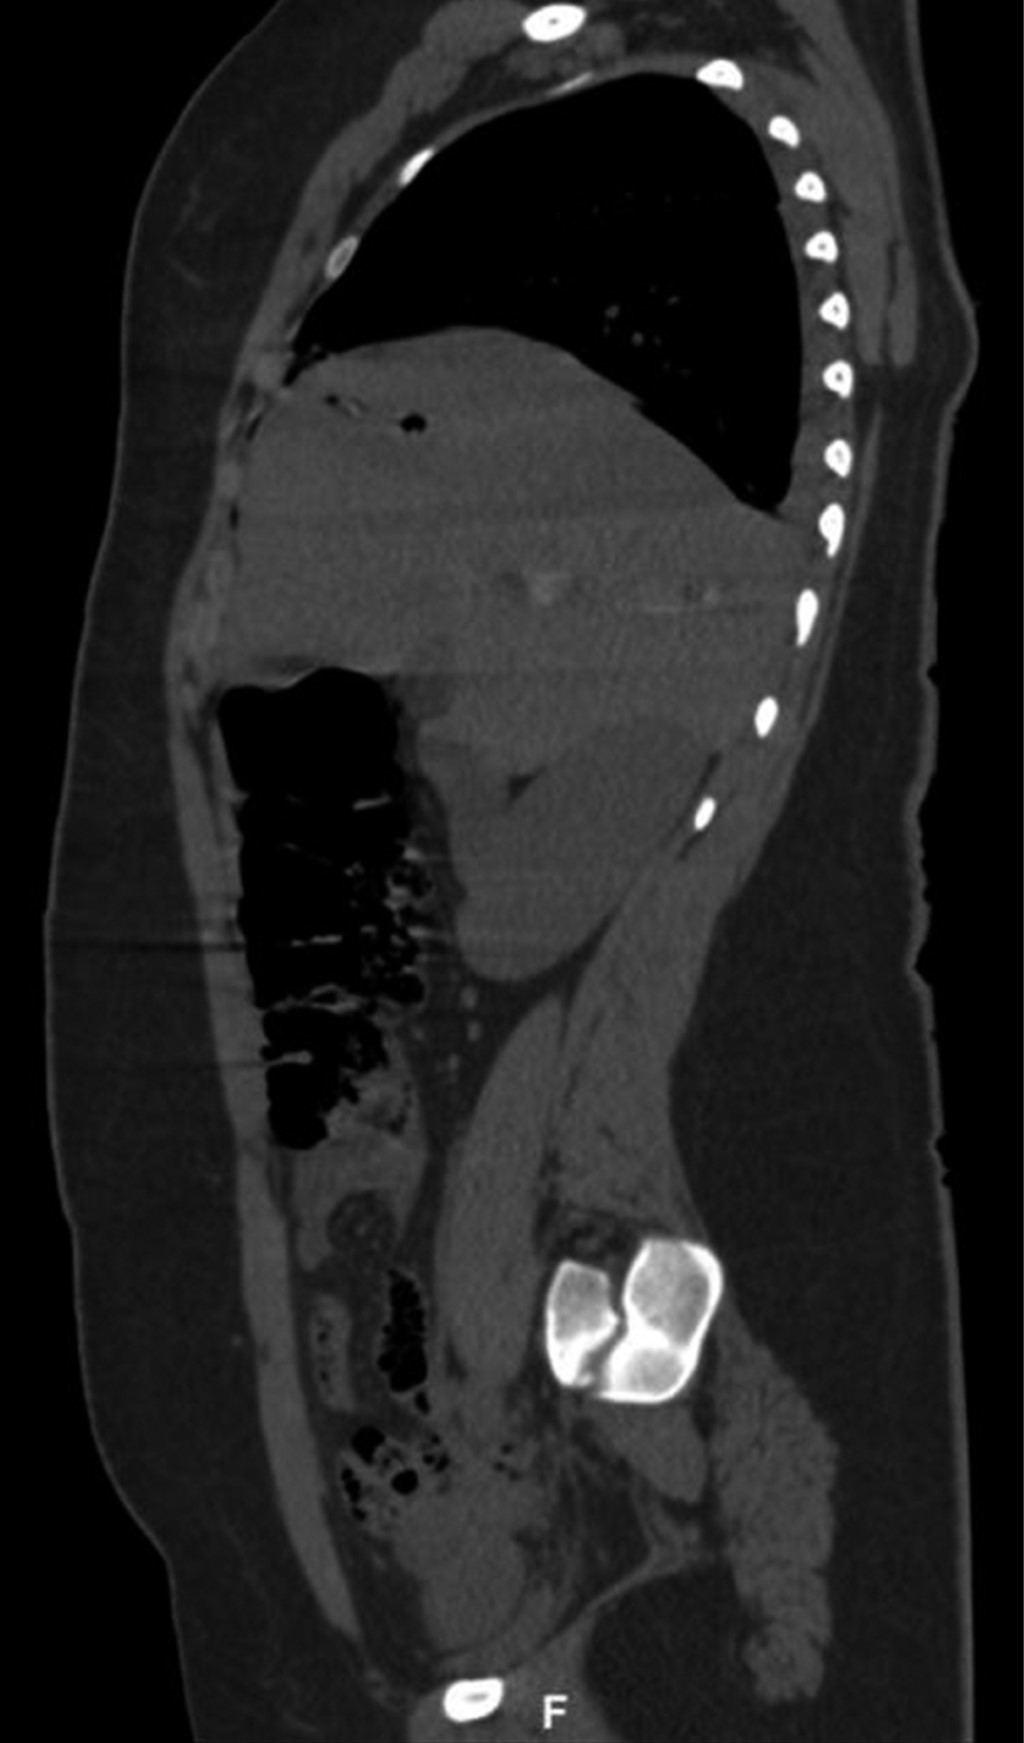

En la exploración física, sus signos vitales fueron los siguientes: frecuencia cardiaca: 74 latidos/minuto; tensión arterial: 98/67 mmHg; frecuencia respiratoria: 19/minuto, temperatura de 36 °C y saturación de oxígeno: 98%. En tórax presentaba un orificio de entrada de PAF en el cuadrante superior externo de la mama derecha (Figura 1), los campos pulmonares estaban bien ventilados. El abdomen era plano, con peristalsis, blando y sin dolor a la palpación. La biometría hemática reportó lo siguiente: hemoglobina: 12.8 g/dl, hematocrito 36.4% y leucocitos: 6,400/ml. La radiografía de tórax descartó neumotórax (Figura 2). Una TC de tórax y abdomen mostró un cuerpo extraño metálico alojado en la línea parasagital derecha a nivel de la doceava vértebra torácica (Figura 3), sin lesión pulmonar ni diafragmática (Figuras 4 y 5); en abdomen se observó un trayecto por PAF con lesión hepática grado IV de 12 cm por 2.3 cm en los segmentos IV, VII y VIII de Couinaud (Figura 5), líquido libre escaso, sin lesión de ningún otro órgano (Figuras 3, 5 y 6). Veinticuatro horas después se le realizó una TC de control, evidenciando la lesión hepática sin colección subcapsular ni extravasación activa a la aplicación del medio de contraste, sin aumento del líquido libre. Ante la correlación de estos hallazgos con la estabilidad clínica, se egresó a la paciente al cuarto día de su ingreso. Sin complicaciones un mes después de su alta.

Figura 5